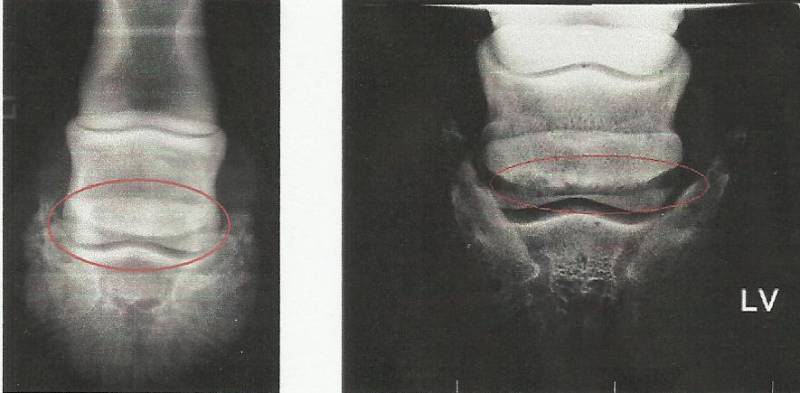

Het hoefbeen, kroonbeen en de diepe buigpees glijden over de achtervlakte van het straalbeen. Tussen de diepe buigpees en het straalbeen bevindt zich ook nog een slijmbeurs. Ligamenten die het straalbeen met de beenderen van de ondervoer verbinden hoort er ook bij.

Met hoefkatrolontsteking word er gezegd dat er een aandoening van de benige en weke delen van het hoefkatrolgebied. Hoefkatrol ontstaat door een overbelasting van het hoefkatrol apparaat. Het ontstaan er van: